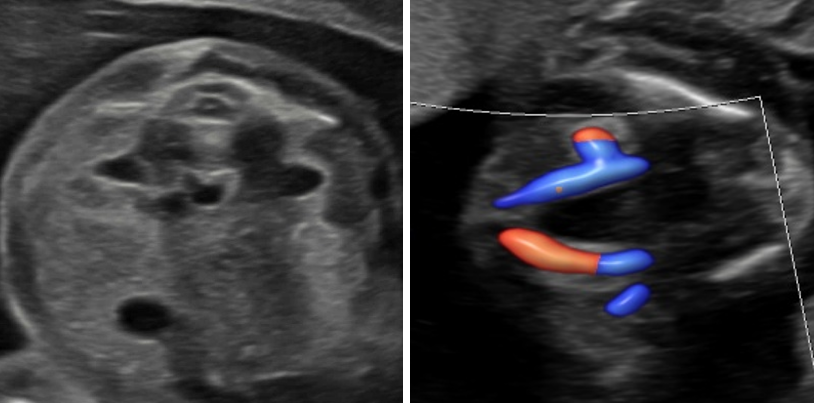

Doppler

Bei dieser Untersuchung messen wir die Durchblutung in der Nabelschnur und anderen Blutgefäßen, um die Versorgung Ihres Kindes zuverlässig einzuschätzen und zu überwachen. Je nach Fragestellung ist diese Untersuchung ab 11 SSW möglich.